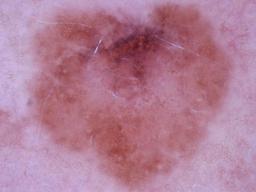

Melanoma and Nevus Dermoscopy Images with Confirmed Histopathological Diagnosis

- Name: Melanoma and Nevus Dermoscopy Images with Confirmed Histopathological Diagnosis

Description:

Collection defined by Dr. Jorge A. Rios-Duarte for a research project.